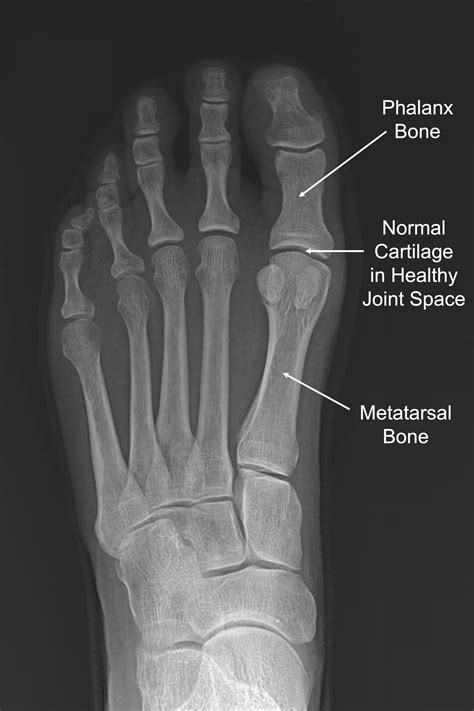

The big toe joint acts as a hinge, allowing the toe to flex and extend during the gait cycle. It is composed of the head of the first metatarsal bone and the base of the proximal phalanx of the big toe. Encased within this structure are cartilage, ligaments, and a joint capsule, all of which work in harmony to facilitate movement.